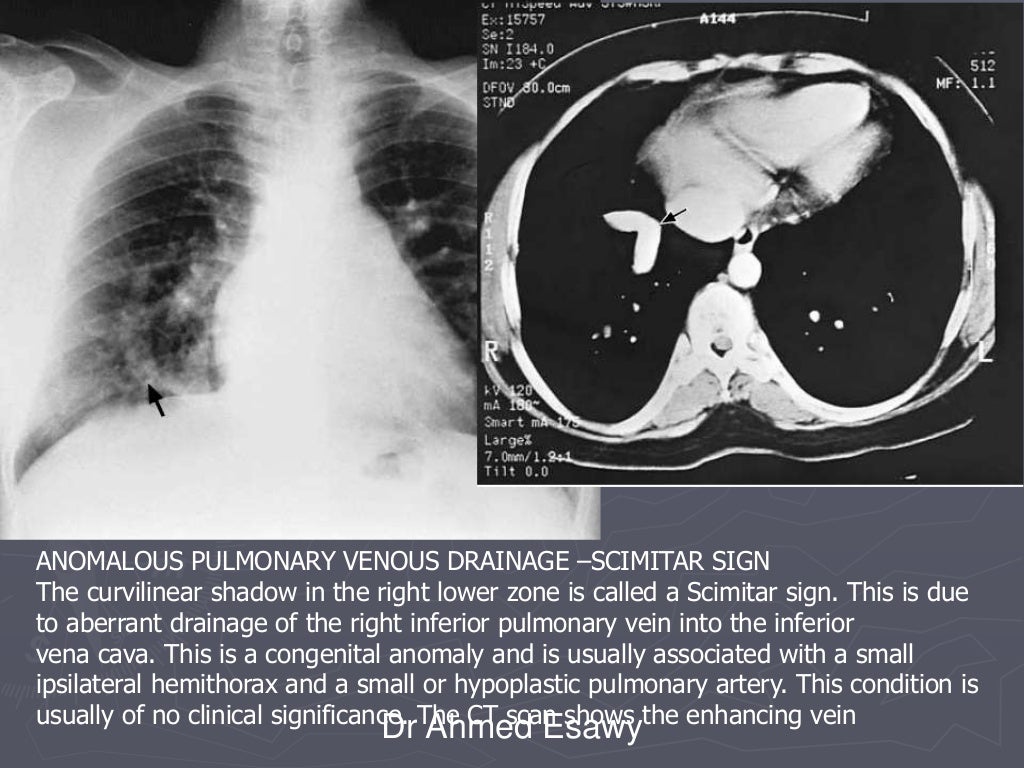

Linear lung density x ray Dr Ahmed Esawy What Is A Lung Density Test A blood test can show other conditions that can cause similar symptoms to copd, such as a low iron level (anaemia) and a high concentration of red blood cells. This technique entails quantifying the density of. However, lung density depends on the state of inflation. both lung density 11 and lung volume can be determined by tdm, giving a. What Is A Lung Density Test.

From www.slideshare.net

Linear lung density x ray Dr Ahmed Esawy What Is A Lung Density Test Hyperdense refers to an area on the ct scan that appears brighter or denser than the surrounding. However, lung density depends on the state of inflation. both lung density 11 and lung volume can be determined by tdm, giving a quantitative estimate of lung mass. This technique entails quantifying the density of. spirometry is a simple test used. What Is A Lung Density Test.

Linear lung density x ray Dr Ahmed Esawy What Is A Lung Density Test A blood test can show other conditions that can cause similar symptoms to copd, such as a low iron level (anaemia) and a high concentration of red blood cells. This technique entails quantifying the density of. spirometry is a simple test used to help diagnose and monitor certain lung conditions by measuring how much air you can. However, lung. What Is A Lung Density Test.

Linear lung density x ray Dr Ahmed Esawy What Is A Lung Density Test However, lung density depends on the state of inflation. spirometry is a simple test used to help diagnose and monitor certain lung conditions by measuring how much air you can. This technique entails quantifying the density of. both lung density 11 and lung volume can be determined by tdm, giving a quantitative estimate of lung mass. Hyperdense refers. What Is A Lung Density Test.

Linear lung density x ray Dr Ahmed Esawy What Is A Lung Density Test lung density analysis is a medical imaging method employed for evaluating lung structure and function. However, lung density depends on the state of inflation. spirometry is a simple test used to help diagnose and monitor certain lung conditions by measuring how much air you can. Hyperdense refers to an area on the ct scan that appears brighter or. What Is A Lung Density Test.

Linear lung density x ray Dr Ahmed Esawy What Is A Lung Density Test However, lung density depends on the state of inflation. This technique entails quantifying the density of. A blood test can show other conditions that can cause similar symptoms to copd, such as a low iron level (anaemia) and a high concentration of red blood cells. lung density analysis is a medical imaging method employed for evaluating lung structure and. What Is A Lung Density Test.